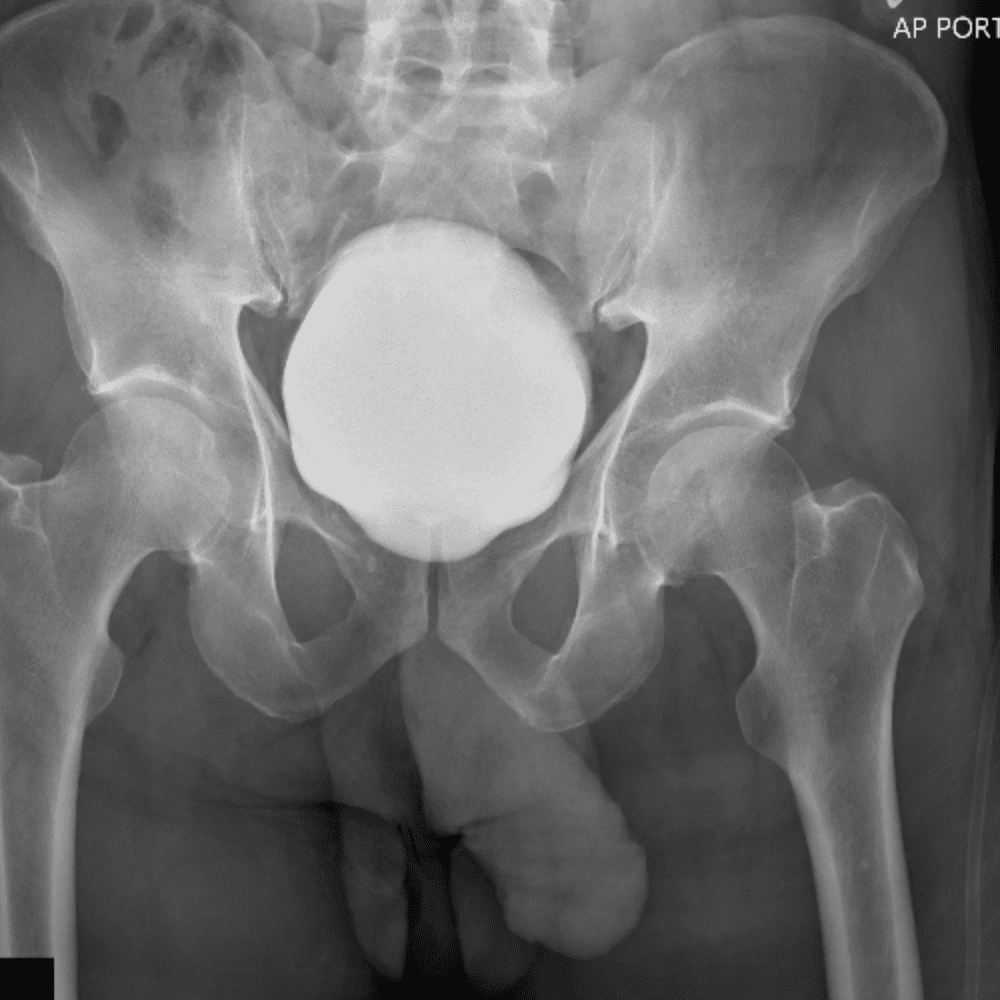

通过包含微妙或困难的病例和一些正常病例来模拟值班。